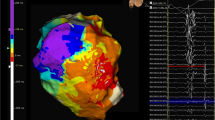

Substrate map data analysis is summarised in Table 3. There was a significant reduction in the average bipolar BZA of 4.4 cm2/12% (p = 0.026) and bipolar LPA of 3.5 cm2/83% (p = 0.0449) post-ablation. Figure 2a shows representative substrate and LP maps pre- and post-ablation. There was a significant reduction in the mean bipolar (0.14 mV (p = 0.0007)) and unipolar (0.59 mV (p = 0.0072)) voltages of the ATA post-ablation with Fig. 2b highlighting the reduction in signal attenuation from the DTA catheter. Complete procedural success was achieved in 9 procedures. No post-ablation stimulation protocol was performed at the end of 1 procedure due to a steam pop occurring after 48 min of ablation resulting in pericardial tamponade requiring drainage.

Representative case. Substrate and LP maps are shown in a representative case pre- and post-ablation, using standard LV bipolar voltage criteria, with the ATA highlighted with the dashed white line. Post-ablation, the BZA has been effectively reduced from 7.5 to 3.2 cm2 with a corresponding increase in the DSA. The pre-ablation LPA (5.8 cm2) has been completely eliminated. The mean bipolar voltage of the ATA pre-ablation was 0.43 mV and effectively reduced to 0.36 mV post-ablation. b Electrogram amplitude attenuation of the bipolar LP signal from the DTA distal high-resolution electrode is shown (LP = late potential; ATA = ablation target area; BZA = borderzone area; DSA = dense scar area)